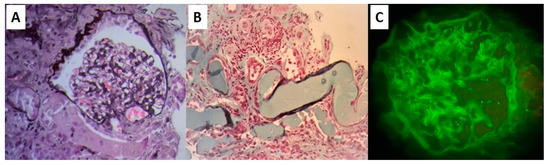

2. Case Report